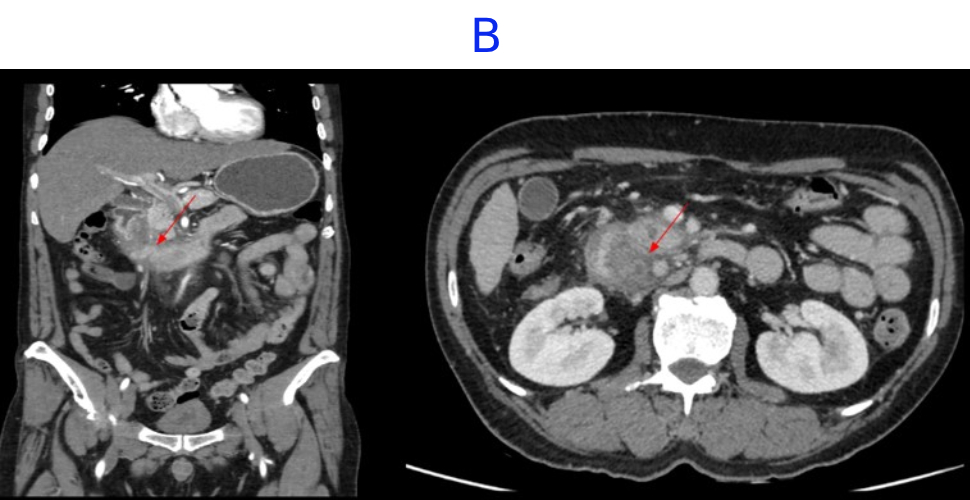

- A. Circumferential irregular submucosal wall thickening noted in D2 and D3 segment of duodenum causing luminal narrowing.

- B. Few hypoenhancing areas within the medial wall of duodenum. Uncinate process of pancreas appears oedematous.